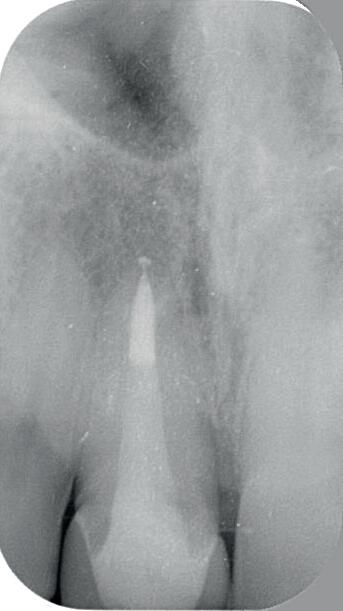

9: Röntgenfoto met kanaalvulling en twee glasvezelstiften

10: Composietopbouw gevormd onder bestaande kroon

Bij de controle na 3 jaar (afbeelding 13) is de pocketdiepte verder afgenomen tot 4 mm (afbeelding 14), de gingiva is stevig en er is geen bloeding na sonderen. De CBCT laat duidelijk ingroei van het bot zien (afbeelding 15 en 16). De laatste röntgenfoto dateert van 14 jaar na de behandeling (afbeelding 17), er zijn geen klachten en de parodontale conditie is stabiel.